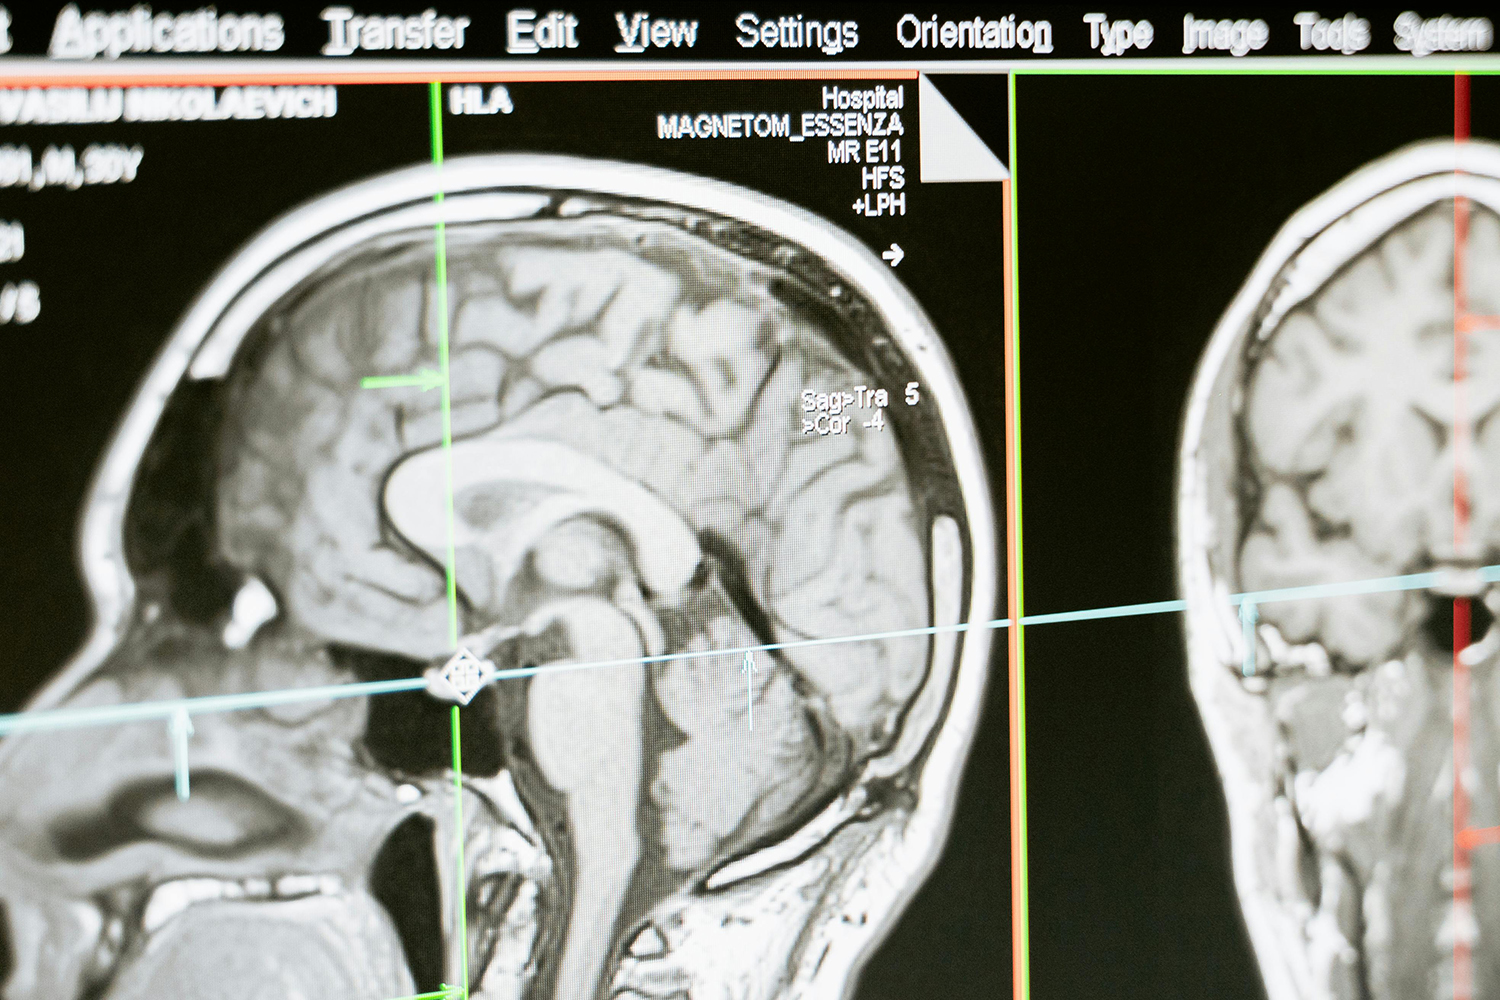

磁共振(MR)作为一种强大的成像技术已凭借其无辐射、分辨率高(尤其针对软组织成像)被广泛的应用于大部分疾病的诊断。

核磁共振成像(MRI)目前普遍应用于医学检测成像中,具有无辐射损伤的安全性,可任意方位断层扫描等技术灵活性,加以涵盖质子密度、弛豫、加权成像以及多参数特征的优势,已成为当代临床诊断中最有力的检测手段之一,然而临床发现某些不同组织或肿瘤组织的弛豫时间相互重叠,导致诊断困难。

核磁共振成像因其具有无创、快速、高解析率、高对比度等特点,在临床上广为使用。特别是在肿瘤的诊断中,该技术利用病变组织和正常组织物理特性的不同而获得的结构、功能影像,已经成为原发肿瘤和肿瘤转移早期诊断中不可或缺的重要依据。